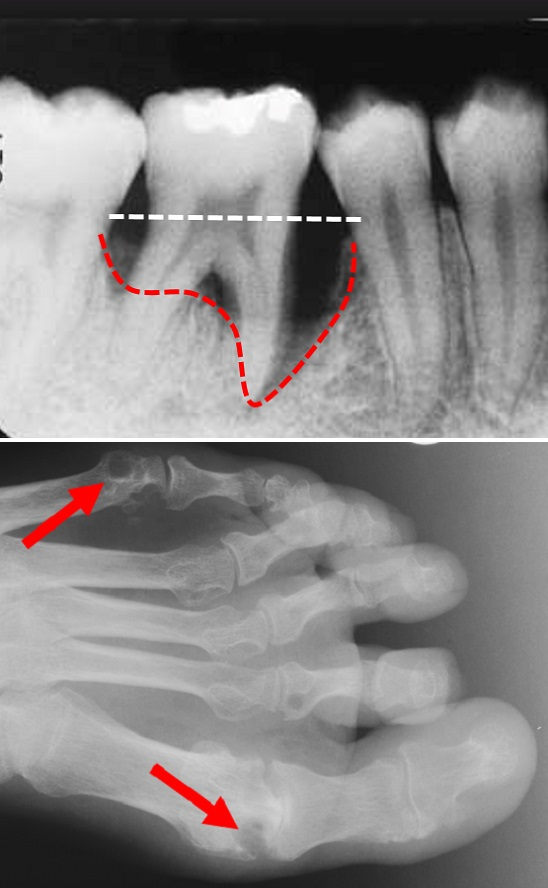

I den övre röntgenbilden visar vit linje normal käkbensnivå vid en kindtand i underkäken. Individen har parodontit (tandlossning) och har därför förlorat käkbensstöd (röd linje). Undre röntgenbild visar en fot med typiska bendestruktioner (röda pilar) orsakade av reumatoid artrit. Bilder: Pernilla Lundberg och Solbritt Rantapää-Dahlqvist.

Inflammationsdriven benförlust är karakteristiskt för både tandlossningssjukdom och ledgångsreumatism. Trots att det finns olikheter i vad som orsakar inflammationsprocessen vid tandlossningssjukdom respektive ledgångsreumatism är det idag fastställt att det finns ett samband mellan de två sjukdomarna.

Resultaten, som nu presenteras i Arthritis & Rheumatology, visar för första gången att de individer som senare utvecklar ledgångsreumatism uppvisar en högre grad av käkbensförlust. Individer med ledgångsreumatism utvecklar också en högre grad av käkbenförlust över tid. Bland de individer som senare utvecklade ledgångsreumatism upptäcktes den allra högsta graden av benförlust hos de individer som dessutom hade förhöjda nivåer av den bennedbrytningsdrivande molekylen RANKL i blodet.